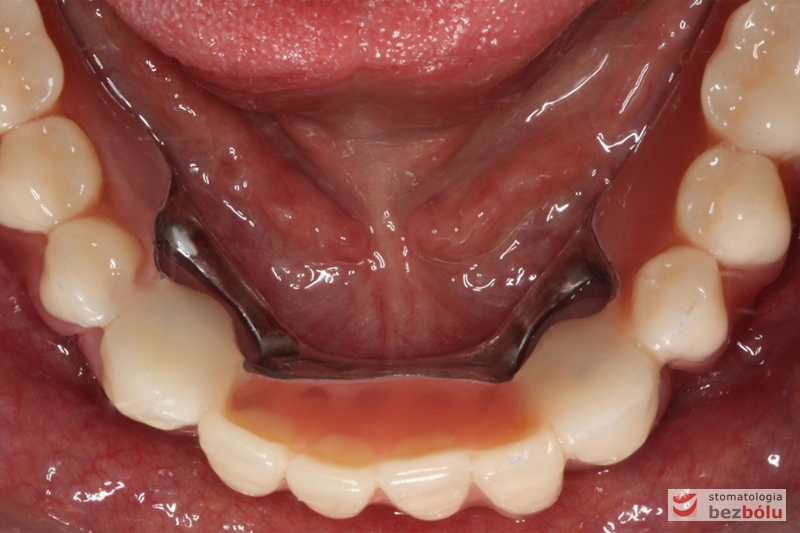

Odbudowa protetyczna w żuchwie - precyzyjne dopasowanie pracy protetycznej do podłoża

Odbudowa protetyczna w żuchwie – precyzyjne dopasowanie pracy protetycznej do podłoża